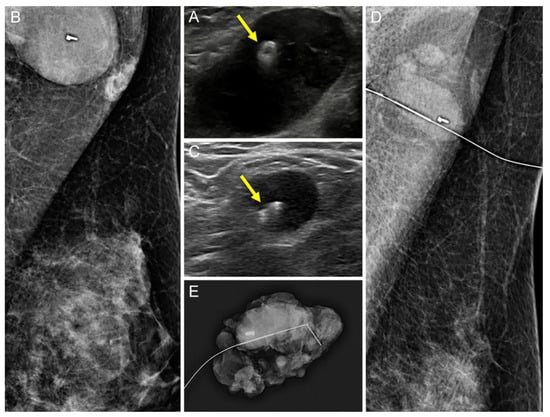

Comparison of the Ultrasound Visibility of Tissue Markers in Metastatic Lymph Nodes after Neoadjuvant Chemotherapy in Patients with Breast Cancer

3.1. Comparison of the US Visibility between the Two Tissue Markers after NAC

3.2. Comparison of the Successful Excision Rates of the Clipped Lymph Nodes between the Two Tissue Markers